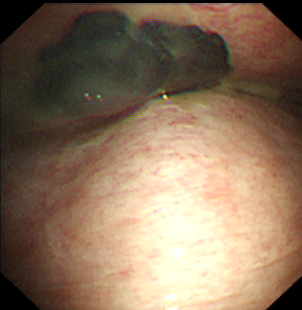

近年来,贵州航天医院各科室紧跟医学前沿,不断强技术、补短板,大力开展新技术、新项目,完成了许多高精尖、高难度、本地区“首例”的技术,填补了医院医疗技术空白,满足了群众日益增长的医疗需求。 贵州航天医院呼吸与危重症医学科是贵州省内呼吸疾病治疗规模最大,诊疗项目最全的呼吸疾病品牌科室,呼吸介入技术达到了全国先进水平,在贵州省内处于领先的地位。 本期,我们将为大家带来呼吸与危重症医学科特色技术——内科胸腔镜技术诊断和治疗胸腔疾病。 案例分享 患者苟某某,因劳累、气促,不明原因胸腔积液在某县一医院采取反复抽水等治疗手段效果不佳,当地医院考虑到患者年龄大(77岁),基础疾病较多,病情复杂,结合当地诊疗水平能力情况,建议转到上一级医院诊治,通过我院与该院建立的呼吸专科联盟绿色通道转入了我院。 患者入院后,呼吸与危重症医学科第一时间复查胸部CT,提示:右肺中叶、左肺感染,纤维化灶,左侧中量胸腔积液,右后侧胸膜轻度增厚,心包少量积液;并完善心电图、血常规、凝血功能、生化指标等术前检查。经科室专家团队集体讨论,得出患者左侧胸腔积液可能原因:结核?恶性?其他?冠心病、心功能不全、高血压病3级(高危组)、陈旧性肺结核复发?肺部感染;为进一步明确诊断,在充分评估、做好术前准备及应急预案、与患者及家属沟通的情况下,决定为患者进行内科胸腔镜检查术。 科室在患者入院第3天便实施了内科胸腔镜检查术,经检查取活检,病理不排除胸膜间皮瘤,送遵义医科大学附属医院病理会诊后诊断:胸膜间皮瘤。明确诊断后,科室专家团队为患者制定了个体化的治疗方案,患者病情很快得到有效控制,最终满意出院。半年后,医院通过电话回访,患者病情稳定,生活质量明显改善。 什么是内科胸腔镜 内科胸腔镜(medical thoracoscopy,MT)是一项微创诊断和治疗胸腔疾病的重要技术。主要应用于无创方法不能确诊的胸腔积液和胸膜疾病,通过局部麻醉后在胸壁做一个小切口,插入胸腔镜,直接观察胸膜、肺表面、纵隔等部位的病变情况,可进行活检、粘连松解及胸膜固定等操作。具有创伤小、恢复快、诊断准确性高等优点。 内科胸腔镜原理 内科胸腔镜是一项利用现代光学技术和成像技术的侵入性操作技术,应用电子支气管镜、硬质或软硬结合(半硬)的胸腔镜的一种电子内窥镜,末端装有连接着显示屏的微型摄像头。通过胸壁1-2cm左右的小切口,将内科胸腔镜及专用器械(戳卡套管)通过小切口进入胸腔,微型摄像头将胸腔内的情况投射到显示屏幕上,医生可以通过镜头全面、直观地观察患者胸腔内情况,了解胸膜病变确切位置和形态改变,还可对胸膜上的病变进行活检及治疗的操作技术,安全、微创、几乎无痛地“揭秘”不明原因的胸腔积液。 内科胸腔镜技术优势 (一)安全性高:仅需局部浸润麻醉,并发症发生率相对较低,对患者的身体条件要求较低。 (二)操作简便:操作时间短,痛苦少,患者耐受好。 (三)微创性:切口小,对患者身体损伤小,术后疼痛轻,恢复快。 (四)高分辨率成像:清晰显示胸腔内细微病变,提高诊断准确性。 (五)可直视操作:直接观察病变,进行精准活检和治疗。 (六)适用范围广:可用于不明原因胸腔积液、胸膜疾病、肺部疾病等的诊断和治疗。 (七)费用低:与外科胸腔镜比较费用低廉。 内科胸腔镜技术是贵州航天医院呼吸专科和呼吸介入诊疗优势的一部分,在2016年率先开展了内科胸腔镜技术,年手术量约100余例,已建立了快速、精准、规范、有效的一体化诊疗服务体系。目前呼吸与危重症医学科内科胸腔镜技术广泛应用于不明原因胸腔积液、气胸、脓胸的诊断和肺癌、弥漫性恶性胸膜间皮瘤等的分期,恶性或复发性胸腔积液、早期脓胸、自发性顽固性气胸的治疗。 镜下常见表现:单发或多发结节、灰白色弥漫性粟粒样结节、胸膜充血、水肿、胸膜增厚及纤维分隔或粘连带形成。 诊断方面: 胸腔积液的病因诊断。内科胸腔镜对恶性胸腔积液的诊断率可高达90%以上,胸腔镜对结核性病变诊断率极高,几乎达到96%以上。 腺 癌 恶性淋巴瘤 软骨肉瘤胸膜转移 滑膜肉瘤胸膜转移 结核性胸膜炎 治疗方面: 脓胸 肺大泡 贵州航天医院 呼吸与危重症医学科学科带头人 廖江荣 国务院政府特殊津贴专家 二级教授 主任医师 贵州航天医院副院长 国家级学术任职: 第二届中国医药教育协会介入微创专业委员会呼吸分会副主任委员 中国抗癌协会肿瘤微创治疗专业委员会常务委员 中国防痨协会结核病转化医学专业分会常务委员 第一届中国人体健康科技促进会呼吸介入专委会常务委员 中国医疗保健国际交流促进会结核病学分会第三届委员会常务委员 中国抗癌协会肿瘤微创治疗专业委员会粒子治疗学组第四届委员会委员 中华医学会结核临床专业委员会内镜介入委员 中华医学会放射学分会第十五届委员会介入学组呼吸系统介入专业委员会委员 北京健康促进会中青年专家委员会胸部疾病精准活检分委会副主任委员 中国医师协会介入医师分会第二届委员会肿瘤消融专业委员会委员 中国结核病防治综合质量控制专家指导委员会委员 亚洲冷冻治疗学会常务委员 世界内镜医师协会呼吸内镜协会常务理事 内镜临床诊疗质量评价专家委员会委员 “西部呼吸介入联盟”副理事长 专业擅长: 贵州航天医院 呼吸与危重症医学科简介 贵州航天医院呼吸与危重症医学科以呼吸危重症和介入呼吸病学为强力推手,以肺部感染性疾病及肺癌、肺小结节的早期精准诊疗、慢性呼吸疾病康复治疗为特色,以人才团队建设为核心的科室发展模式,现已成为省内呼吸疾病治疗规模最大,诊疗项目最全的呼吸疾病品牌科室。是贵州省医学重点学科、临床医学重点专科建设单位,遵义市首批呼吸重点学科、重点专科建设单位。是国家卫健委能力建设和继续教育肿瘤微创介入建设中心、贵州省县级医院微创介入培训中心、遵义市呼吸疾病临床医学中心。是国家呼吸医疗质量控制与管理哨点医院、遵义市呼吸内科专业医疗质量控制中心。是中国医药教育协会介入微创呼吸分会呼吸介入技术培训中心单位;国家卫健委海医会呼吸分会ROSE专委会“诊断性介入肺脏病学快速现场评价”培训基地;中国肺癌防治联盟“贵州航天医院肺结节诊治”分中心,中国人体健康科技促进会呼吸介入技术培训基地,贵州省中西医结合会呼吸学分会呼吸介入专委会主委单位。 基本情况 平均每年开展气管镜诊疗约4000例,经皮肺穿刺介入诊疗近千例,开展的项目包括经支气管镜(软、硬)下冷冻、氩气刀、高频电刀、球囊扩张、支架置入、超声内镜诊疗等气道介入诊疗技术,经皮肺穿刺活检及肿瘤消融术(微波、冷冻)、ROSE技术、内科胸腔镜诊疗及经血管介入诊疗技术,且多项呼吸介入诊疗技术在省内处于领先水平。 诊疗范围 航天医院呼吸专科擅长:致力于呼吸系统感染性、疑难性疾病的介入快速精准诊疗;肺癌与肺小结节早期精准诊疗水平项目提升。擅长于呼吸系统(肺)疑难病的诊断及危重病的救治,尤其在肺癌、肺小结节的早期诊断;肺癌综合靶向治疗;肺结核综合诊疗;肺部疾病的介入诊疗在省内处于前沿水平。 咨询热线 (一)呼吸与危重症医学科一病区 医生办公室:27677317 护士站:28614217 (二)呼吸与危重症医学科二病区 医生办公室:28691274 护士站:28690442 (三)呼吸与危重症医学科三病区 医生办公室:28692417 护士站:28690461 (四)呼吸与危重症医学科四病区 医生办公室:28616402、27677582 护士站:28614987、27677862